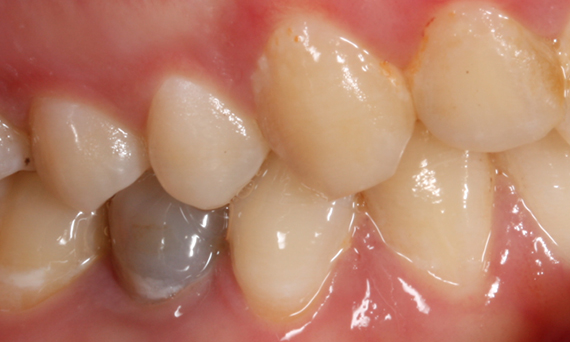

Rehabilitación del cuadrante

Dos coronas CEREC Tessera y dos inlays

En una sola visita de cuatro horas, se realizó la restauración de dos coronas y dos inlays, que tenían 15 años. El paciente quedó muy satisfecho con el muy buen resultado estético.

Antes: Obturaciones insuficientes en el segundo cuadrante. Las restauraciones tenían alrededor de 15 años.

Después: Coronas fabricadas chairside hechas de CEREC Tessera (dientes 26/27). Inlays para los dientes 24 y 25 hechas de bloques de composite.

Dr. Andreas Bindl

Zúrich, Suiza